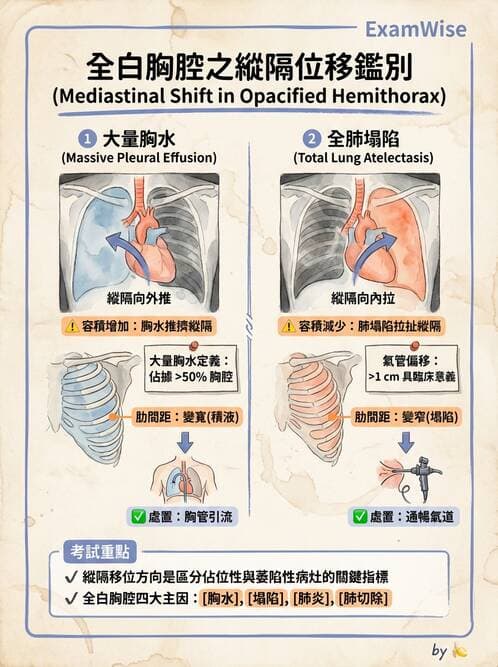

本題聚焦於胸腔內「容積增加」(pleural effusion)與「容積減少」(atelectasis)在胸部X光上的放射徵象差異,並進而決定是否要放置胸管(tube thoracostomy)以引流胸腔積液。

以上為典型「大量胸腔積液」表現,因流體為占位性病灶,隨著體腔壓力推擠,可見縱隔結構向對側轉移 (en.wikipedia.org)。

這些為「整葉或整肺萎陷」(complete atelectasis)典型特徵,因肺容積減少,惹得縱隔結構往同側移動 ([wikidoc.org](https://www.wikidoc.org/index.php/Atelectasis_chest_x_ray?ut